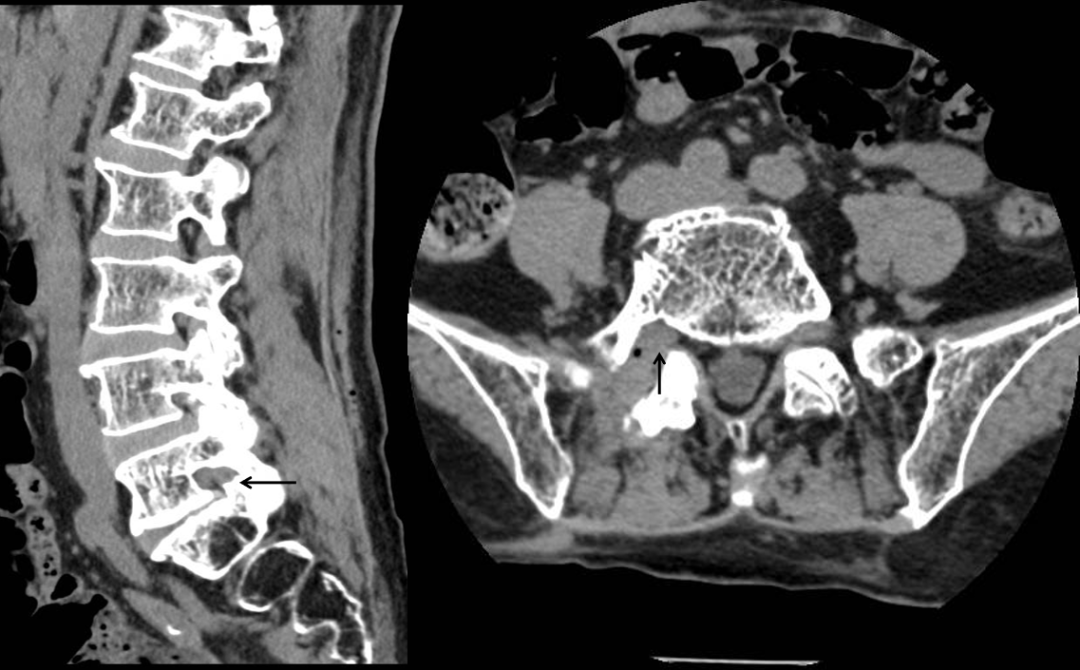

接诊后,中山三院脊柱外科派驻中山三院粤东医院的专家刘仲宇主任指导团队为苏女士进行了系统评估。通过详细的病史询问、体格检查并结合影像学资料,刘主任敏锐发现其右下肢疼痛根源并非此前其他医院诊断的“腰椎间盘突出”、“肌肉劳损”或者“神经系统病变”,而很可能是由L5-S1右侧椎间孔狭窄导致的右侧L5神经根受压所引起。“椎间孔是神经根穿行的通道,当这个空间因骨质增生、韧带肥厚等原因变窄时,神经就会被卡住,引发剧烈疼痛。”刘主任解释道。

为了进一步明确诊断,团队为患者实施了选择性右侧L5神经根造影及封闭检查,在透视下将药物精准注射至疑似病变神经根周围,以达到暂时麻痹病变神经根的目的。注射药物前患者在手术室坐2分钟即出现右下肢疼痛难忍的情况,而注射后立即让患者再次尝试坐位7分钟后仍未出现右下肢不适。说明右侧L5神经根就是病变神经根,证实了诊疗团队的病因推测,明确了诊断。

术前CT